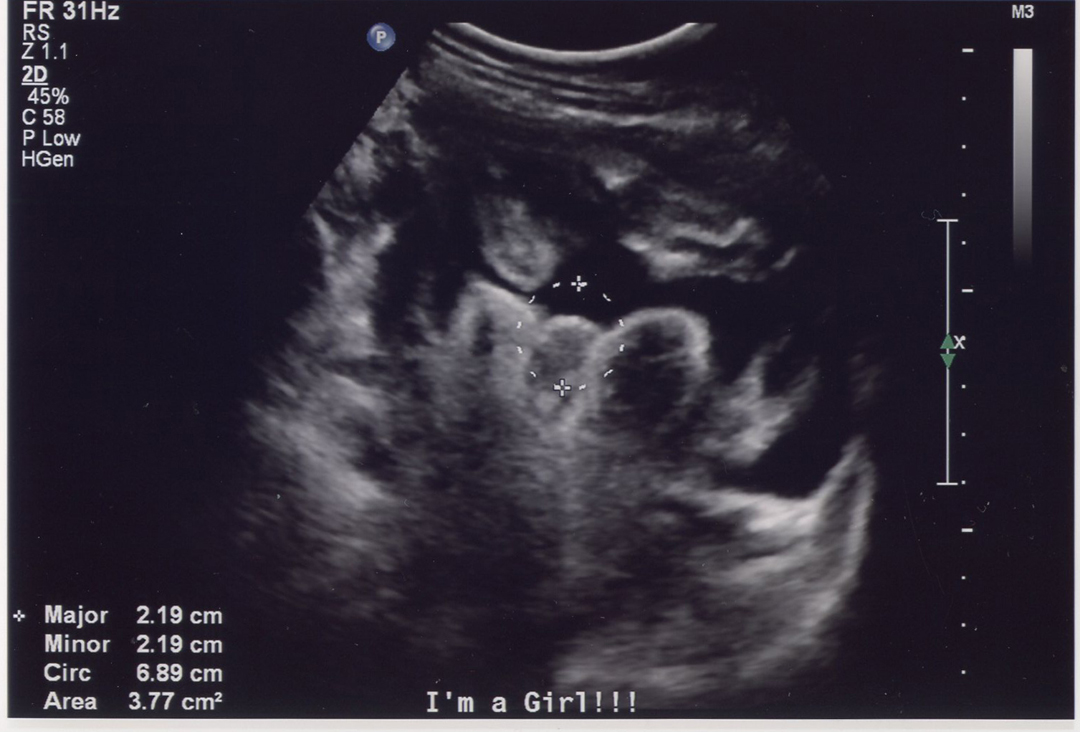

We'll see if I'm uploading these images correctly. :) Top image is from my 20-week scan, the bottom one is at 25 weeks (same hospital, same radiology department, but different ultrasound techs using different machines). I'm 30 weeks now and my doctor did a quick ultrasound today to check baby's position and she, too, confirmed girl.

Attachment 6795